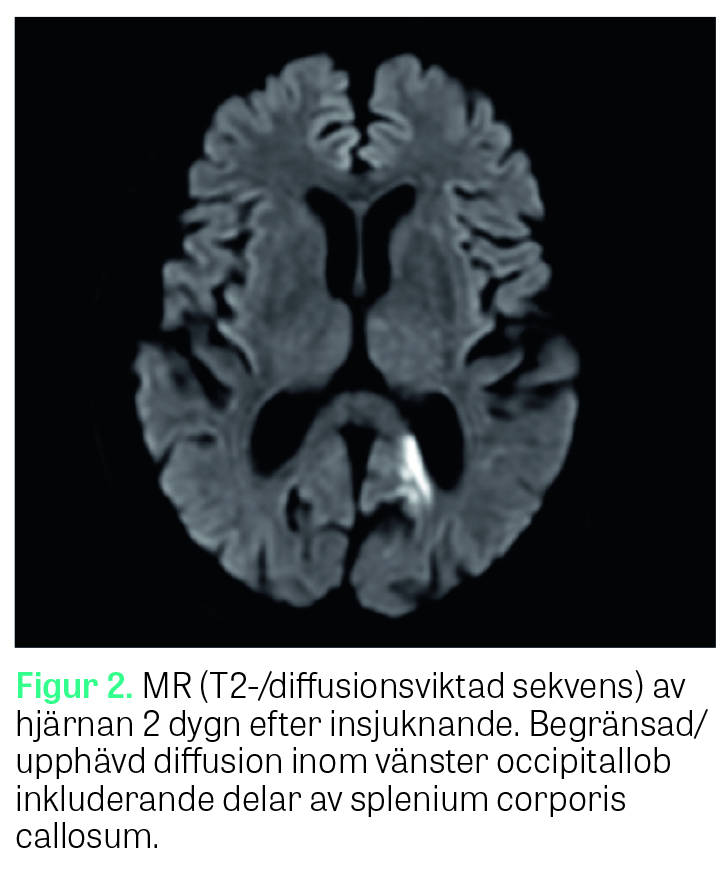

Vid klinisk undersökning på avdelningen av neurolog ett dygn senare var patienten generellt välmående. Han var helt orienterad och uppskattades till RLS 1/GCS 15. Inga motoriska eller sensoriska avvikelser uppdagades. Patienten påtalade att han märkt att han hade svårt att se på sin högra sida, vilket även konfirmerades vid Donders test då en högersidig hemianopsi upptäcktes. Patienten var dock fullt medveten om sin synfältsdefekt och märkte själv hur han kunde kompensera för den genom att vrida huvudet något extra åt höger då han till exempel tittade runt i rummet; således förelåg ingen visuell neglekt. Vid test av läsförmåga förevisas patienten korta »datorskrivna« ord och fraser på ett papper (Riksstrokes manual för NIHSS, National Institutes of Health stroke scale) som hen ska läsa högt. Vid första försöket tolkade patienten orden som siffror, och i stället för att läsa upp till exempel »Du kan«, »Jordnära« och »Jag kom hem från arbetet« läste han »fyra, sju, fem, fyra« etc. Då detta påtalades för patienten gjordes ett nytt försök, och då läste patienten i stället bokstäverna var för sig (»d«, »u«, »k«, »a« etc.). Patienten ­stakade sig ­något vid uppläsningen då han behövde tänka ­efter, men hade inga bekymmer att känna igen bokstäverna efter en stunds betänketid. Det förelåg dock en fortsatt svårighet att sammanfoga bokstäverna till ord. Vid undersökning av skrivförmåga med papper och penna kunde patienten utan bekymmer skriva till exempel »Jag befinner mig på lasarettet« och »Det är februari månad« med både bevarad stavning och handstil. Då patienten direkt efteråt ombads att läsa upp vad han själv skrivit återgick han till att stakande läsa upp bokstäverna var för sig (så kallad »letter by letter reading«) utan att kunna sammanfoga dem till ord. Undersökningen upprepades ett antal gånger för att säkerställa att det inte var patientens högersidiga synfältsdefekt som gjorde att han inte kunde läsa från vänster till höger, men samma mönster upprepades oavsett var i synfältet texten placerades. Patienten kunde på ett adekvat sätt förmedla var i synfältet han hade svårt att se och visade själv hur han kompenserade för detta. Diag­nosen alexi utan agrafi misstänktes och MR hjärna genomfördes som visade på infarktförändringar i vänster (dominant) occipitallob med engagemang av splenium corporis callosum och posteriora talamus (Figur 1–3), överensstämmande med vad man kunnat se i tidigare fallbeskrivningar av alexi utan agrafi [1, 2]. Under vårdtiden uppdagades ett förmaksflimmer på telemetri, vilket bedömdes vara genesen till patientens stroke. Patienten påbörjade behandling med antikoagulantia för att minska risken för ytterligare tromboembolism, erhöll remiss till logoped för att få hjälp med att träna upp läsförmågan och skrevs ut väsentligen välmående från lasarettet ett par dagar senare.

Syndromet alexi utan agrafi (eng: pure alexia), beskrevs av den franske neurologen Joseph Jules Dejerine redan 1892 [3] och i ett flertal fallrapporter därefter [1, 2, 4]. Alexi utan agrafi hör till gruppen »disconnection syndromes«, vilka kan uppstå av skador på nätverken mellan hemisfärerna eller mellan olika delar inom samma hemisfär [5]. De flesta beskrivna fall av alexi utan agrafi har berott på cerebrala infarkter orsakade av ocklusion i arteria cerebri posterior på den dominanta, oftast vänstra, sidan med resulterande infarkt i vänstra visuella kortex och splenium corporis callosum. Förklaringen till fenomenet är att lesionen i splenium stör kopplingen mellan den högra, icke-dominanta sidans visuella kortex och den dominanta sidans gyrus angularis, som med sitt läge i omedelbar anslutning till Wernickes språkförståelse­area har en avgörande betydelse för vår läsförmåga. Den bevarade skrivförmågan förklaras av att den dominanta gyrus angularis i sig själv lämnas intakt vid denna skadelokalisation [1, 6]. Utöver infarcering orsakad av ocklusion i arteria cerebri posterior har syndromet även kunnat ses vid glioblastom [7] och multipel skleros [8].